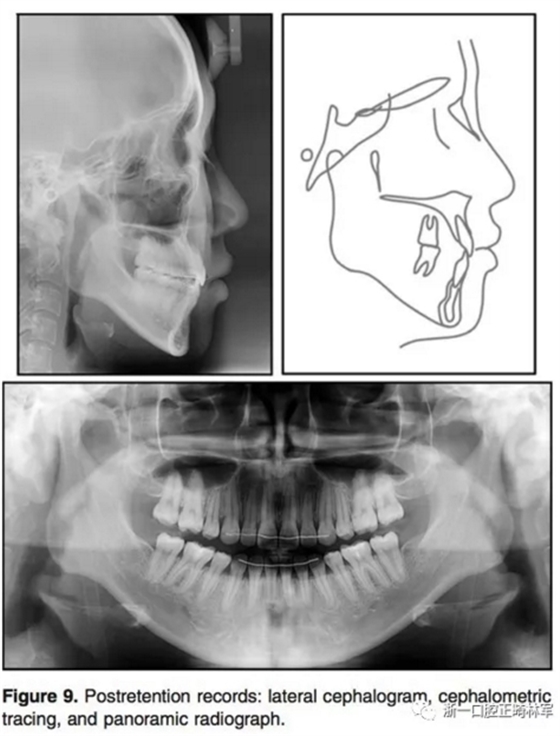

1年的保持,示咬合和面型保持良好。治療后和保持后的重疊像示上下切牙輕微唇傾,導致覆蓋有所增加。上下第一磨牙的位置變化微乎其微。